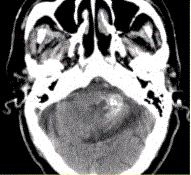

问题 男性,80岁,左耳听力下降伴头晕半年。头CT显示如下图。 关于海绵状血管瘤的描述,错误的是

选项 A.囊性血管性错构瘤,病变内反复出血,无正常神经组织 B.CNS任何位置均可发生,脑实质常见 C.病变内不同时期的出血,大小不一 D.T1WI(典型)爆米花样高信号,病变周边低信号环(含铁血黄素沉积) E.病变明显强化 F.DSA可见血管染色 G.海绵状血管瘤可多发,还可伴有发育性静脉畸形

答案 DEF